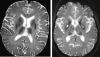

The diagnosis of neurodegeneration with brain iron accumulation (NBIA) can be challenging, particularly given recent advances in NBIA genetics and clinical nosology. Although atypical cases continue to challenge physicians, by considering clinical features along with relevant neuroimaging findings, the diagnosis of NBIA can be made confidently. In addition, the identification of genetically distinct forms of NBIA allows clinicians to better provide prognostic and family counseling services to families and may have relevance in the near future as clinical trials become available. We describe a heuristic approach to NBIA diagnosis, identify important differential considerations, and demonstrate important neuroimaging features to aid in the diagnosis.